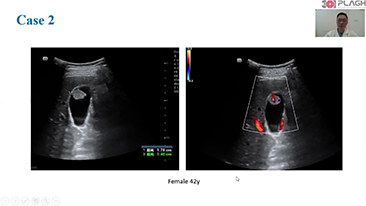

Weniger Stethoskope, mehr Ultraschall?

Optimierte OBG-Workflows sind n?tig, wenn gro?e Patientinnenzahlen im Rahmen von Gesundheitsscreenings bew?ltigt werden sollen. Zum Beispiel sind Fehlbildungen des zentralen Nervensystems (ZNS) eine der h?ufigsten angeborenen Anomalien. Wegen verschiedener f├╝r die Bildgebung ung├╝nstiger Bedingungen, etwa eine schwierige Position des F?tus, ist es besonders schwer, die MSP von 2D-Ultraschall zu erhalten. Aus diesem Grund k?nnen automatisierte Erkennung und Messungen die Scanning-Effizienz deutlich steigern.